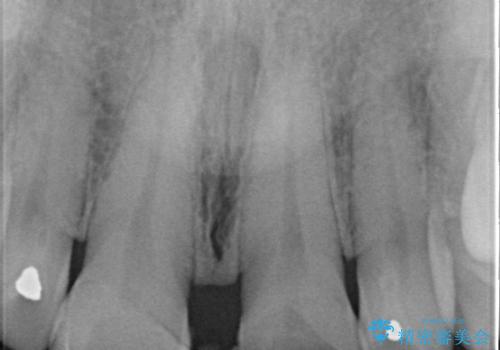

- 前歯のすきっぱを主訴にご来院された患者様です。他院でつめものやラミネートべニア(前歯の表面のみセラミックを貼り付ける)を行っていましたが、頻繁に外れることに悩まれており、クラウン(歯全体をセラミックがつつむ)をご希望されました。また、奥歯に大きな虫歯があり、歯が割れていたため、奥歯の治療も併せて行いました。

右上の歯に関しても、大きな虫歯があったため、前歯の経過観察の間に治療を行いました。